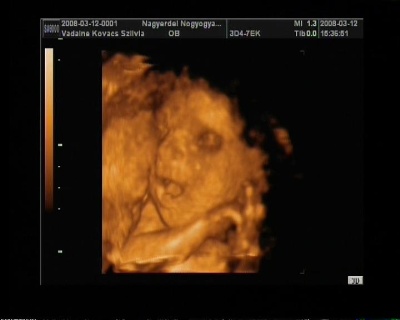

És egy tappancs 2008.03.08 19:45